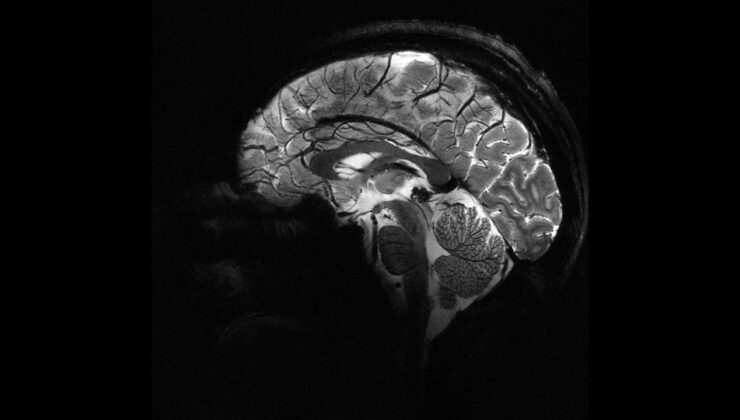

Beyne verilen elektrik akımı bencilliği azaltabilir mi?

Deney sırasında beynin ön ve arka kısımlarında yer alan frontal ve paryetal bölgelere elektrik akımı uygulandı. Bu iki bölge aynı anda uyarıldığında, katılımcıların daha fazla para paylaştığı gözlemlendi.

Bu çalışma, katılımcıların para paylaşma oyunu sırasında beyin aktivitelerinin izlendiği önceki bir araştırmaya dayanıyor. Önceki çalışmada, daha fazla para paylaşıldığında beynin karar verme ve empati bölgelerinin aynı frekansta “iletişim kurduğu” tespit edilmişti. Yeni deneyle birlikte, dışarıdan müdahale ile bu bölgeler arasındaki iletişimin tetiklenebileceği ve insanların daha özverili kararlara yönlendirilebileceği kanıtlanmış oldu.

Araştırma ekibinden Dr. Jie Hu, çalışmanın en yeni yanının neden-sonuç ilişkisini ortaya koyması olduğunu söyledi. Hu, hedeflenmiş ve cerrahi müdahale gerektirmeyen bir stimülasyonla belirli bir beyin ağındaki iletişimin değiştirilmesinin, insanların kendi çıkarları ile başkalarının çıkarları arasındaki dengeyi nasıl kurduklarını doğrudan etkilediğini vurguladı.